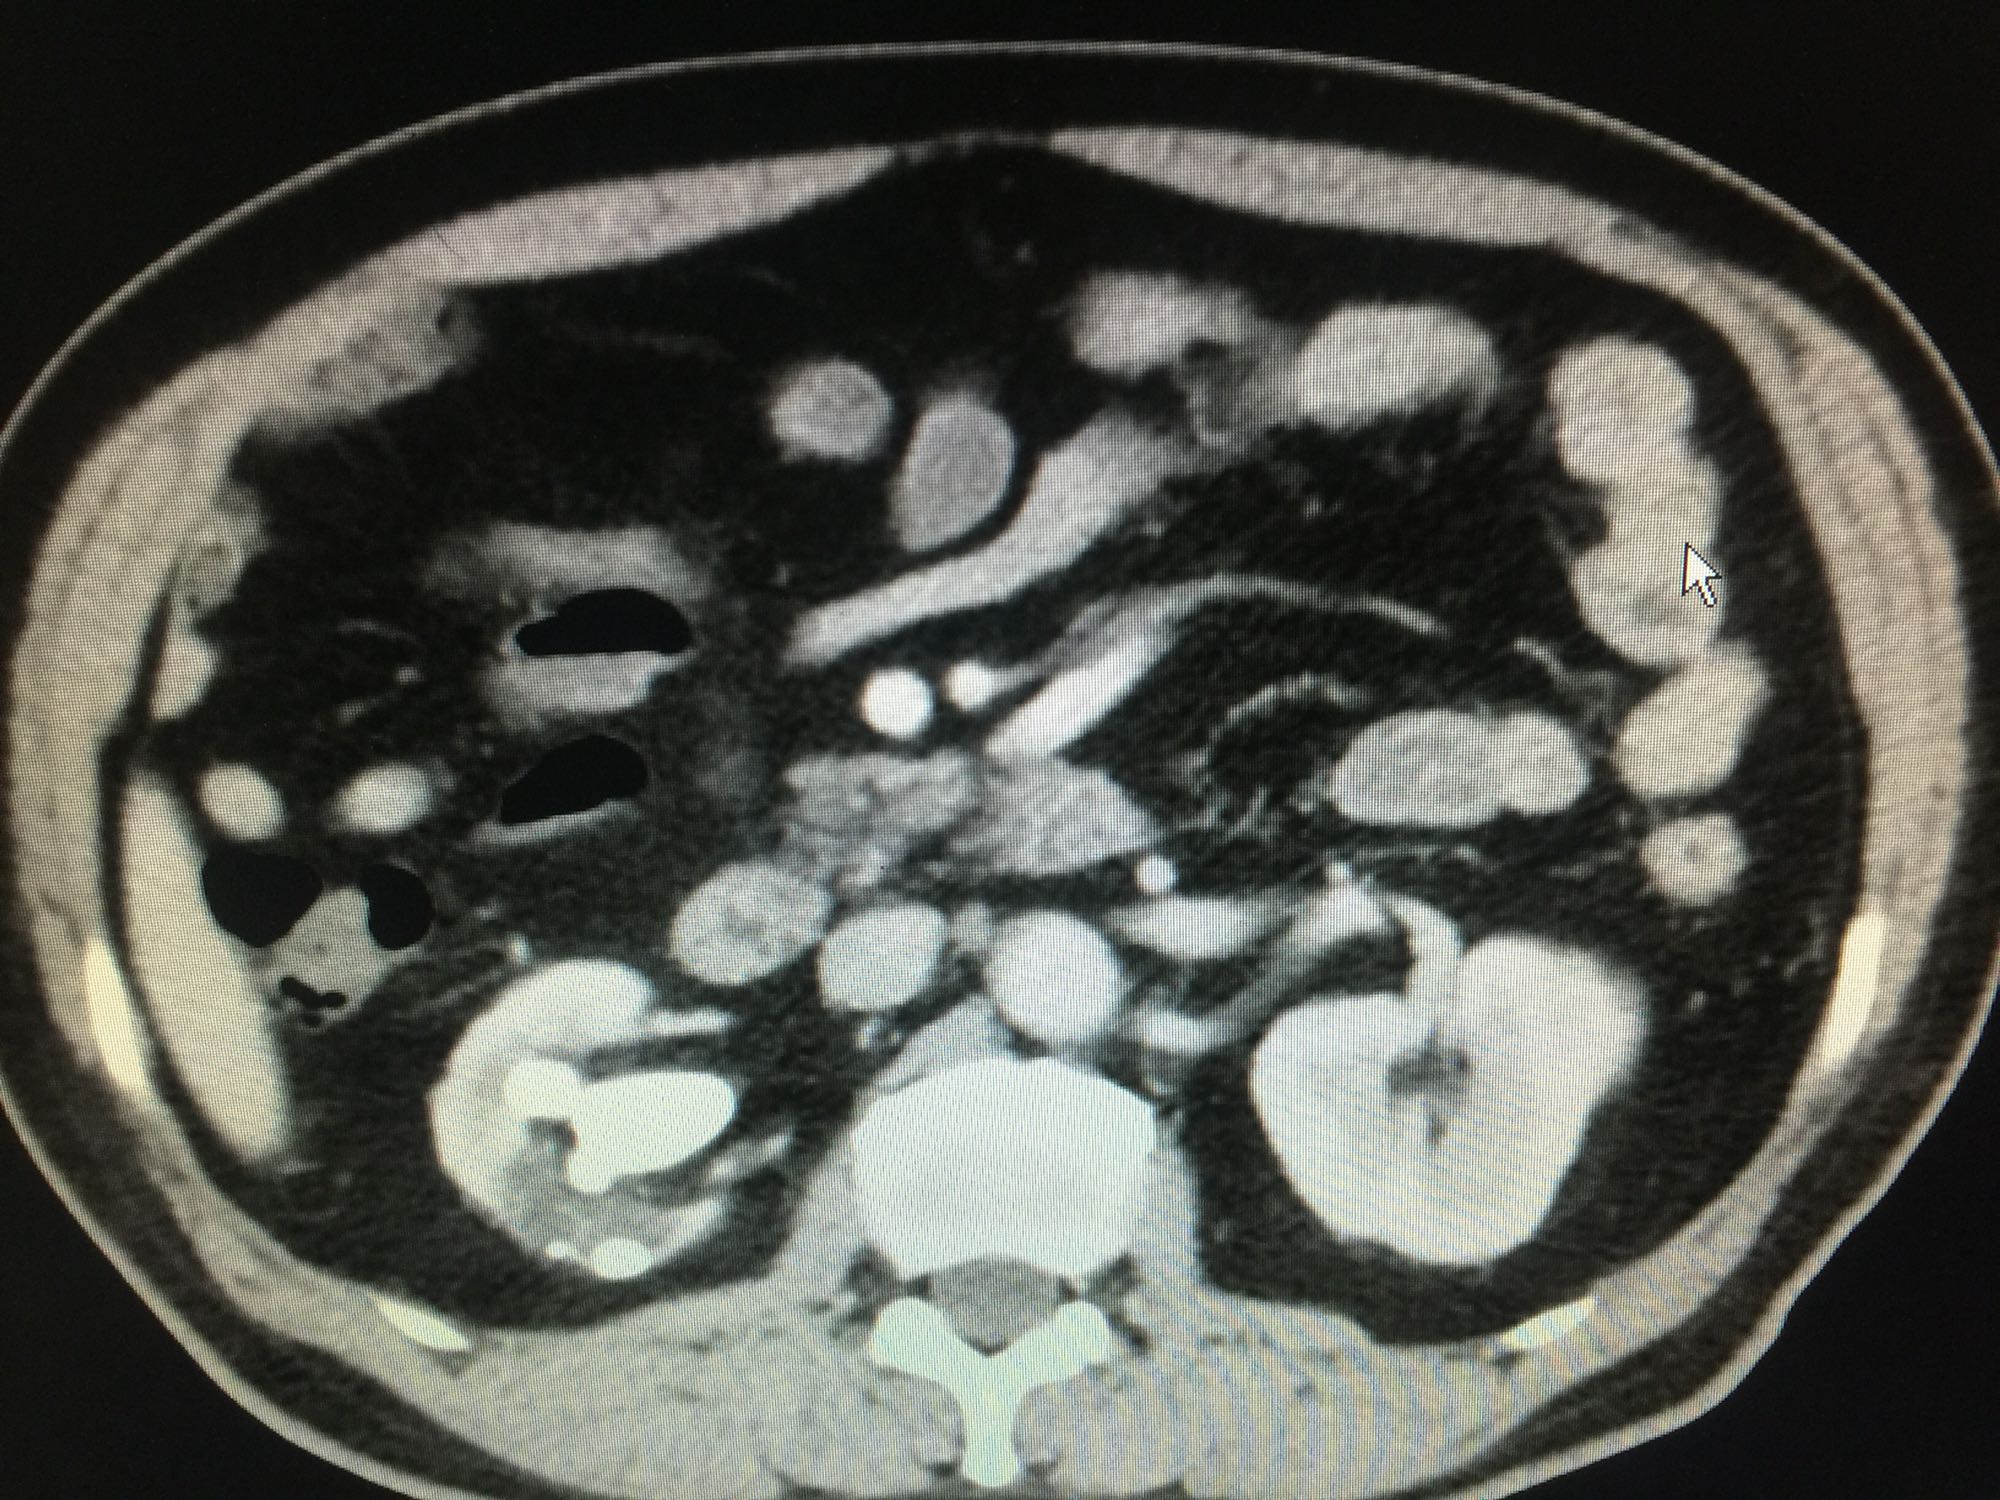

60岁男性 既往无高血压糖尿病等病史 检查发现右侧肾结石10年 10年前检查发现右侧肾结石,直径约1厘米,未给予正规治疗,近日来我院门诊,行彩超发现右肾多发结石,进一步治疗入院。

查体:双肾区无叩压痛,膀胱区无叩压痛,无叩浊,前列腺二度,质地中等,无压痛,无结节。CTU提示右肾铸型结石。ECTL 40,R14.5

右肾铸型结石 予以经皮肾碎石治疗,术后复查平片未见结石残留。